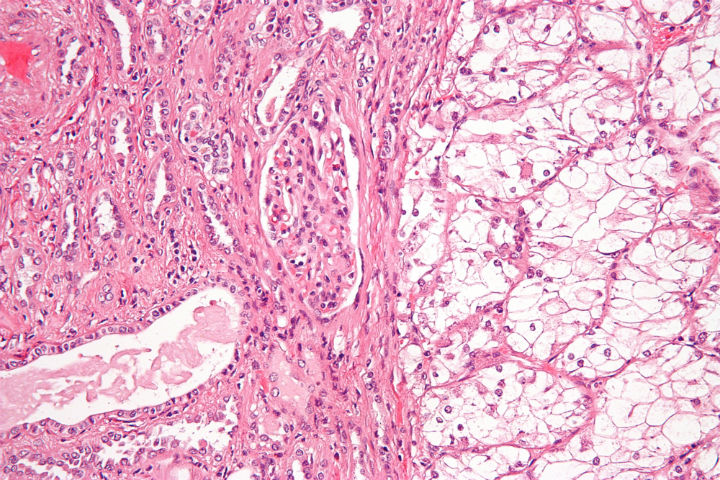

Renal cell carcinoma makes up approximately nine out of ten kidney cancer cases in adults. This type of kidney cancer originates in the lining of the proximal convoluted tubule, which is part of the small tubes in the kidney that transport waste from the blood to the urine. The...